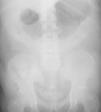

Presentamos el caso de un paciente varón de 84 años, con antecedentes de insuficiencia renal crónica avanzada en sesiones de hemodiálisis. Nos consultan desde el servicio de nefrología por distensión del perímetro abdominal y estreñimiento en las últimas 48h. Solicitamos radiografía de abdomen (fig. 1) visualizando dilatación gástrica, resolviéndose posteriormente con la colocación de una sonda nasogástrica. En esta radiografía, nos llama la atención una imagen parecida a restos de contraste baritado en colon, cerciorándonos de que el paciente no había sido sometido a ninguna prueba de imagen ni se le había dado contraste oral. Revisando en su historial comprobamos que tomaba carbonato de lantano.

Los comprimidos de carbonato de lantano pueden visualizarse claramente en radiografías, su densidad es superior a la del hueso siendo bastante parecida a la del bario. Cuando se realiza una radiografía de abdomen se puede observar material de alta densidad en pacientes que están bajo tratamiento con carbonato de lantano5.